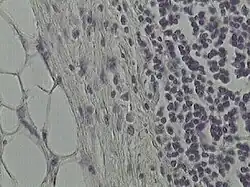

.jpg)

6. Tecido conjuntivo denso não modelado do esôfago

O tecido conjuntivo frouxo suporta estruturas normalmente sujeitas a pressão e atritos pequenos, sendo um tecido muito comum que preenche espaços entre grupos de células musculares, suporta células epiteliais e forma camadas em tomo dos vasos sanguíneos. É também encontrado nas papilas da derme, na hipoderme, nas membranas serosas que revestem as cavidades peritoneais e pleurais e nas glândulas. As células mais numerosas são os fibroblastos e macrófagos, mas todos os outros tipos celulares do tecido conjuntivo também estão presentes, além de fibras dos sistemas colágeno e elástico. Ele tem uma consistência delicada, é flexível, bem vascularizado e não muito resistente a trações.

Já o tecido conjuntivo denso é adaptado para oferecer resistência e proteção aos tecidos. É formado pelos mesmos componentes encontrados no tecido conjuntivo frouxo, entretanto, existem menos células e uma clara predominância de fibras colágenas. Ele é menos flexível e mais resistente à tensão que o tecido conjuntivo frouxo.